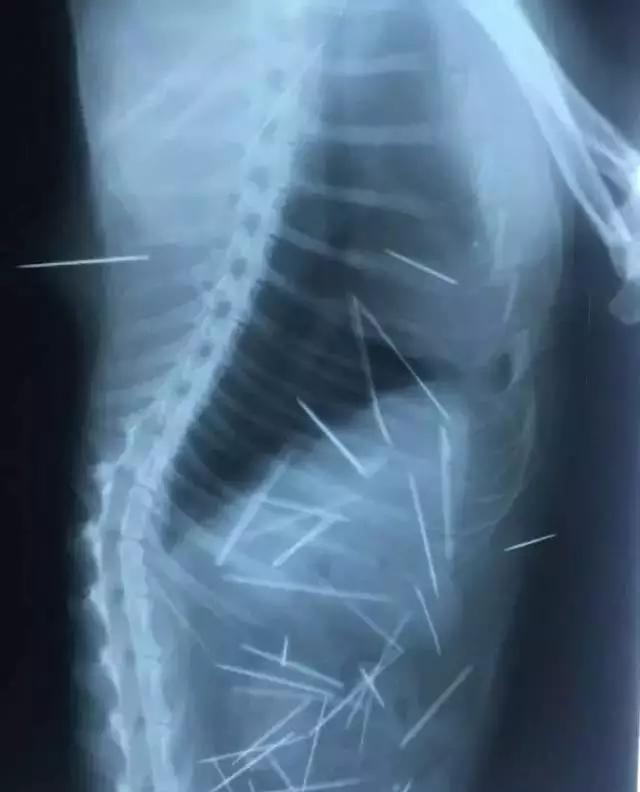

下面这名中国深圳女网友1年多前就收养了一只猫咪。最近,她抚摸猫咪时发现它脖子后方有不正常凸起,猫咪看起来也很痛苦。她带猫咪去看医生,拍摄X光片后才发现它体内有30到40根细针,兽医认为这可能是被空气枪射入的。当时领养猫咪时,这名网友只带它做了血常规猫瘟等检查,不知道还要去照X光片。

这次动物医院连续照了53次X光片,发现猫咪体内有多根细针,有些已经生锈。其中7根针在皮肤和肌肉、3根针和2根断针在胸腔心脏旁边,30根针在腹腔,其中有4根是插入到左侧肾脏。现在这些针已经开始游离,猫咪很痛苦。医生表示手术也只能取出2/3。很多网友不相信这件事,认为不可能养猫一年都没有察觉,甚至认为她想要藉机骗钱。猫咪主人表示,自己并不想要搏版面,这都是实情。经过近4小时的手术,医生共从猫咪体内取出43根针。其中还有一些断掉的针头。从X光片可以看到,猫咪体内布满密密麻麻的细针,看起来怵目惊心。一年多来,猫咪一直忍受针刺的痛苦,它无法说话,只能默默承受。在热心人士的帮忙协助下,猫咪终于做完手术,希望它能够快点好起来,不要再遭遇这样可怕的事。